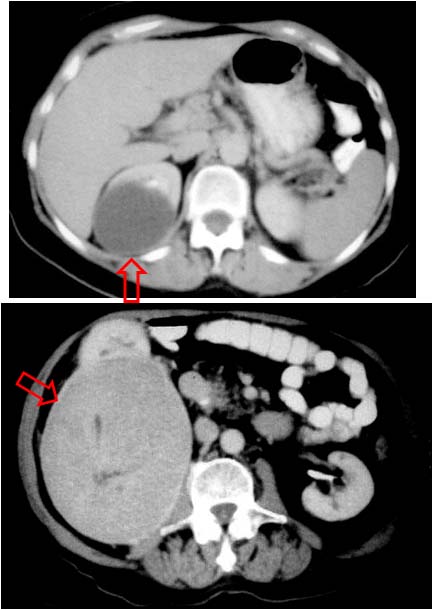

Signo de obstrucción renal crónica en la urografía intravenosa. Se ve mejor en la fase nefrográfica y puede desaparecer en la fase excretora. Se trata de unas bandas radiodensas por fuera del contorno calicial (flechas) que corresponde a la opacificación con contraste de los túbulos intramedulares distorsionados a causa de dilatación pielocalicial por la obstrucción crónica. Para que este signo pueda estar presente se necesita que el riñón conserve cierto grado de función excretora, y este dato es importante, puesto que la función renal es aún recuperable.

anillos de Dunbar2

Otro ejemplo del signo en el polo inferior del riñón derecho.